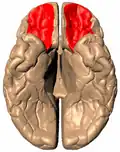

![]() Orbital surface of left frontal lobe (from below) | |